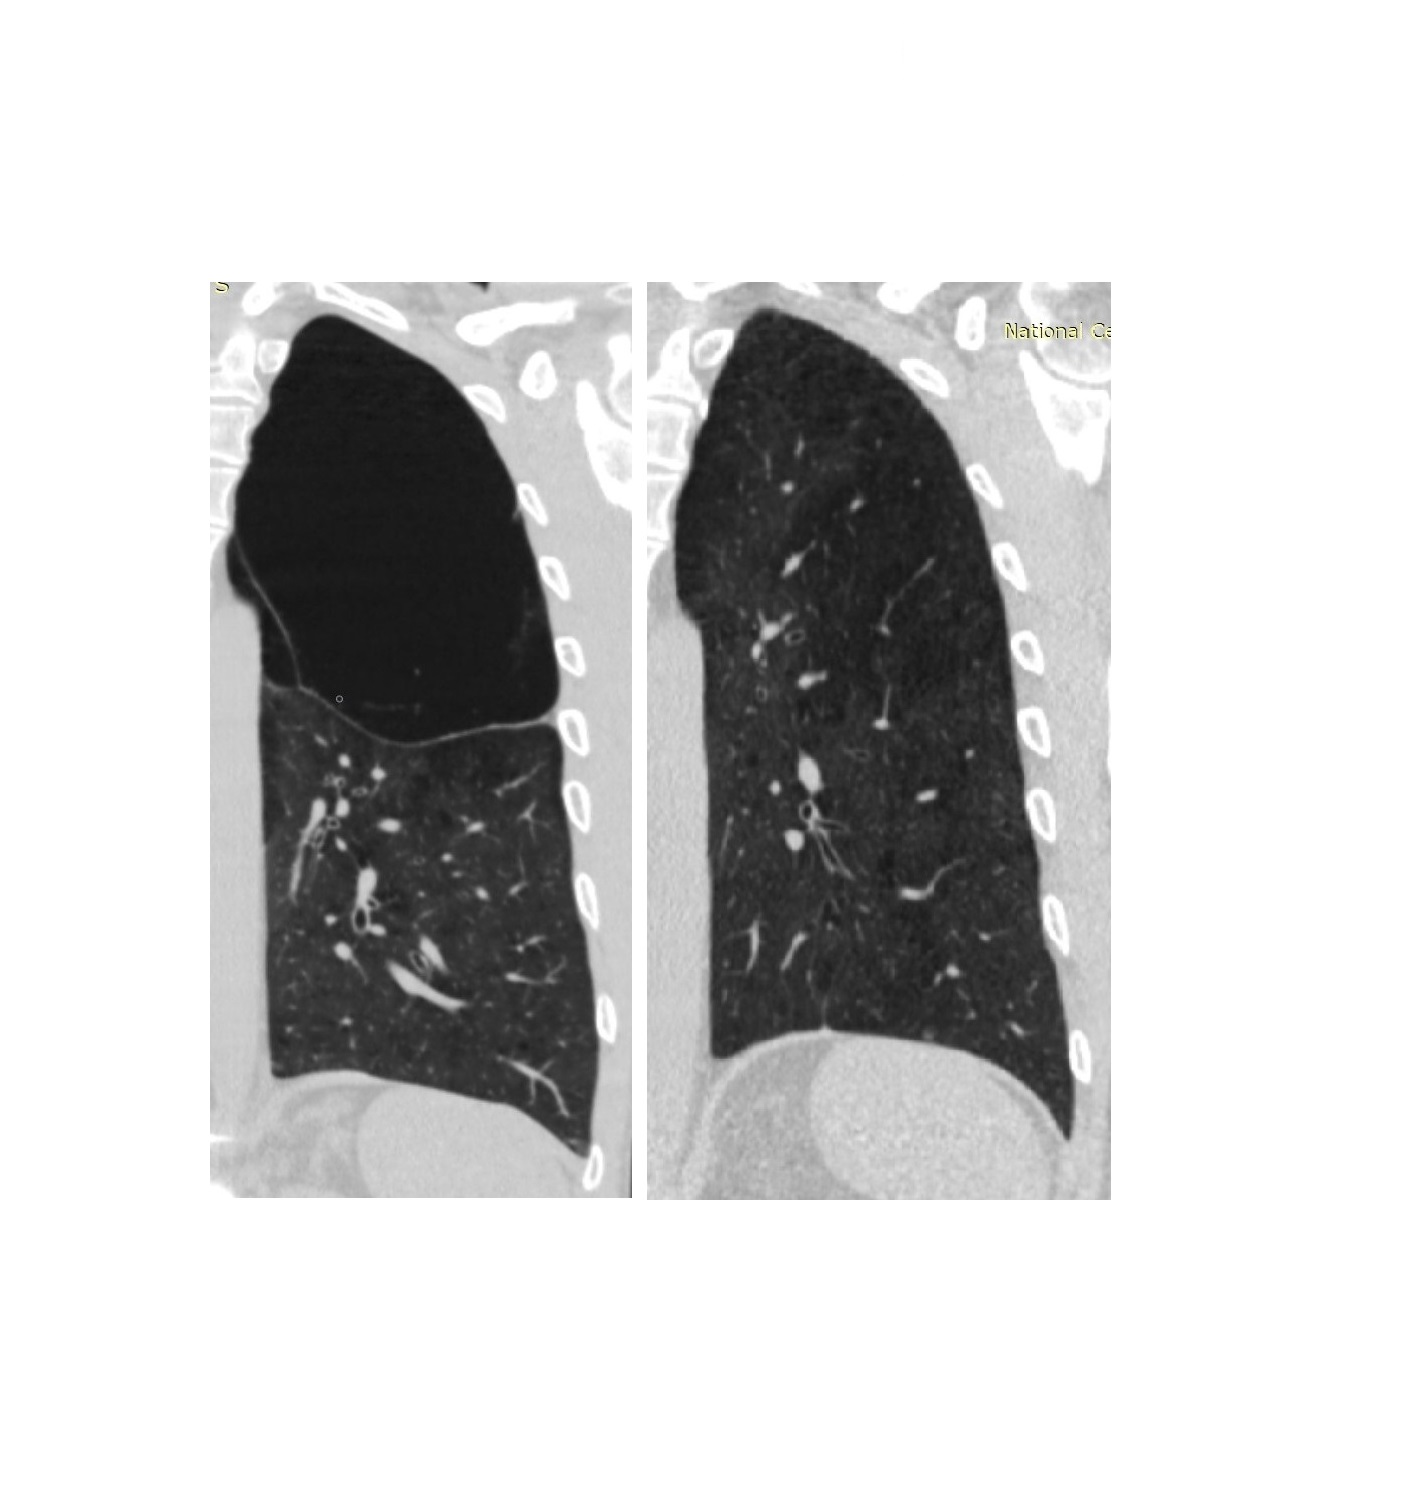

პაციენტი 42 წ მამაკაცი. აქტიური მწეველი. თავს ავად გრძნობს რამოდენიმე თვეა. ჩივილები: ძლიერი ქოშინი ფიზიკურ დატვირთვაზე, ჰაერის უკმარისობა, საერთო სისუსტე. გულმკერდის კტ კვლევით – ორივე ფილტვის ზედა წილებში გაიშვიათებული ფილტვის ქსოვილი, გიგანტური ბულები 10-14 სმ ზომის (16 იან 2020 წ). ბოდიპლეტიზმოგრაფიით – RV (Pleth) 3.90 ლ (Normal Range 1.14-2.49 ლ) (18 თებ 2020 წ). 2020 წლის 18 თებერვალს მარცხენა ფილტვის მოცულობის შემცირების მიზნით პაციენტს ჩაუტარდა რიგიდული ბრონქოსკოპია – სარქვლოვანი ბრონქობლოკაცია. ზოგადი გაუტკივარების ქვეშ ტრაქეაში შეყვანილი იყო Friedel-ის რიგიდული ბრონქოსკოპი. გამოყენებული იყო ტუბუსი N13. მარცხენა ზ/წ ბრონქის სანათურში მოთავსდა სარქვლოვანი ბრონქობლოკატორი N15. მანიპულაციიდან 3 თვის შემდეგ საკონტროლო გულმკერდის კტ კვლევით – მარცხენა ზედა წილში გიგანტური ბულა აღარ ფიქსირდება, ბოდიპლეტიზმოგრაფიით – RV (Pleth) 2.44 ლ (Normal Range 1.14-2.49 ლ) (25 მარ 2020 წ). გულმკერდის კტ კვლევით დადებითი დინამიკა შენარჩუნდა 9 და 12 თვის შემდეგ.